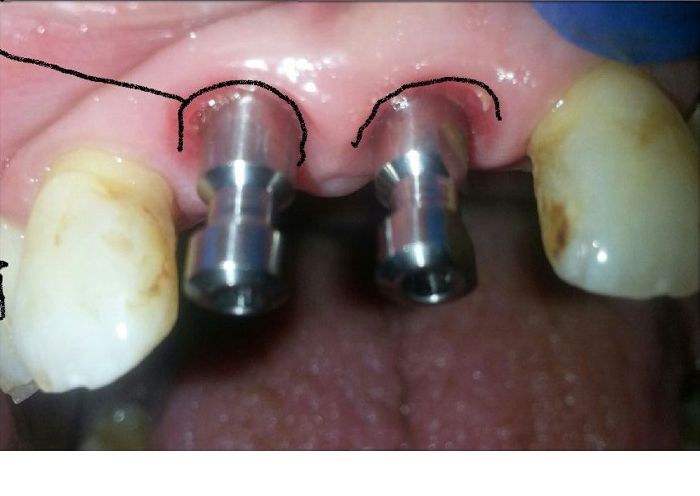

These transfer pegs are used to indicate location of implants to the lab.

Crowns Need To Emerge Through Tissue

Crowns need to emerge through the tissue